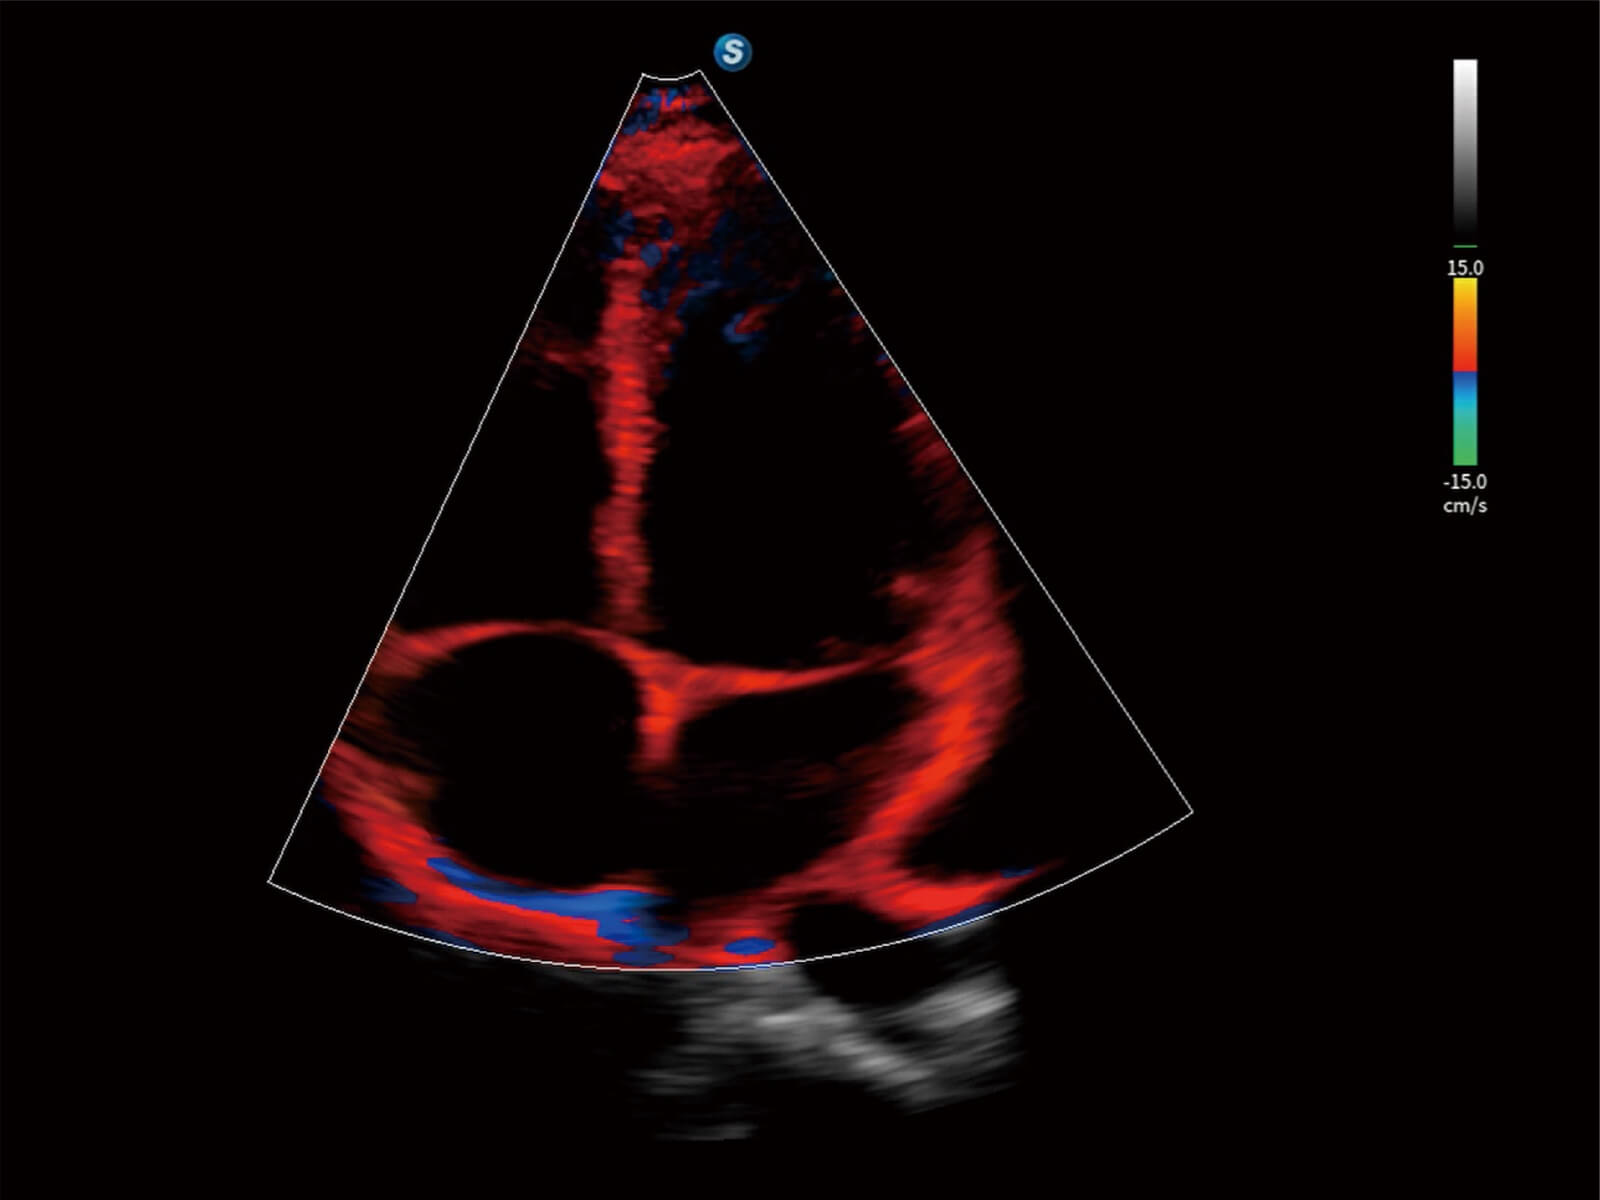

心脏应用

通过光照模型,使二维血流显示出立体的效果,增加血流的敏感性、成束性,减少外溢。可以和其他不同的血流技术联合使用,轻松应对微小血管,增强血流的立体效果,提升视觉敏感性。